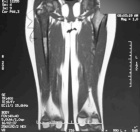

S.C. - 10 year old girl with right leg pain

Zoom image: Radiological image Radiological image.